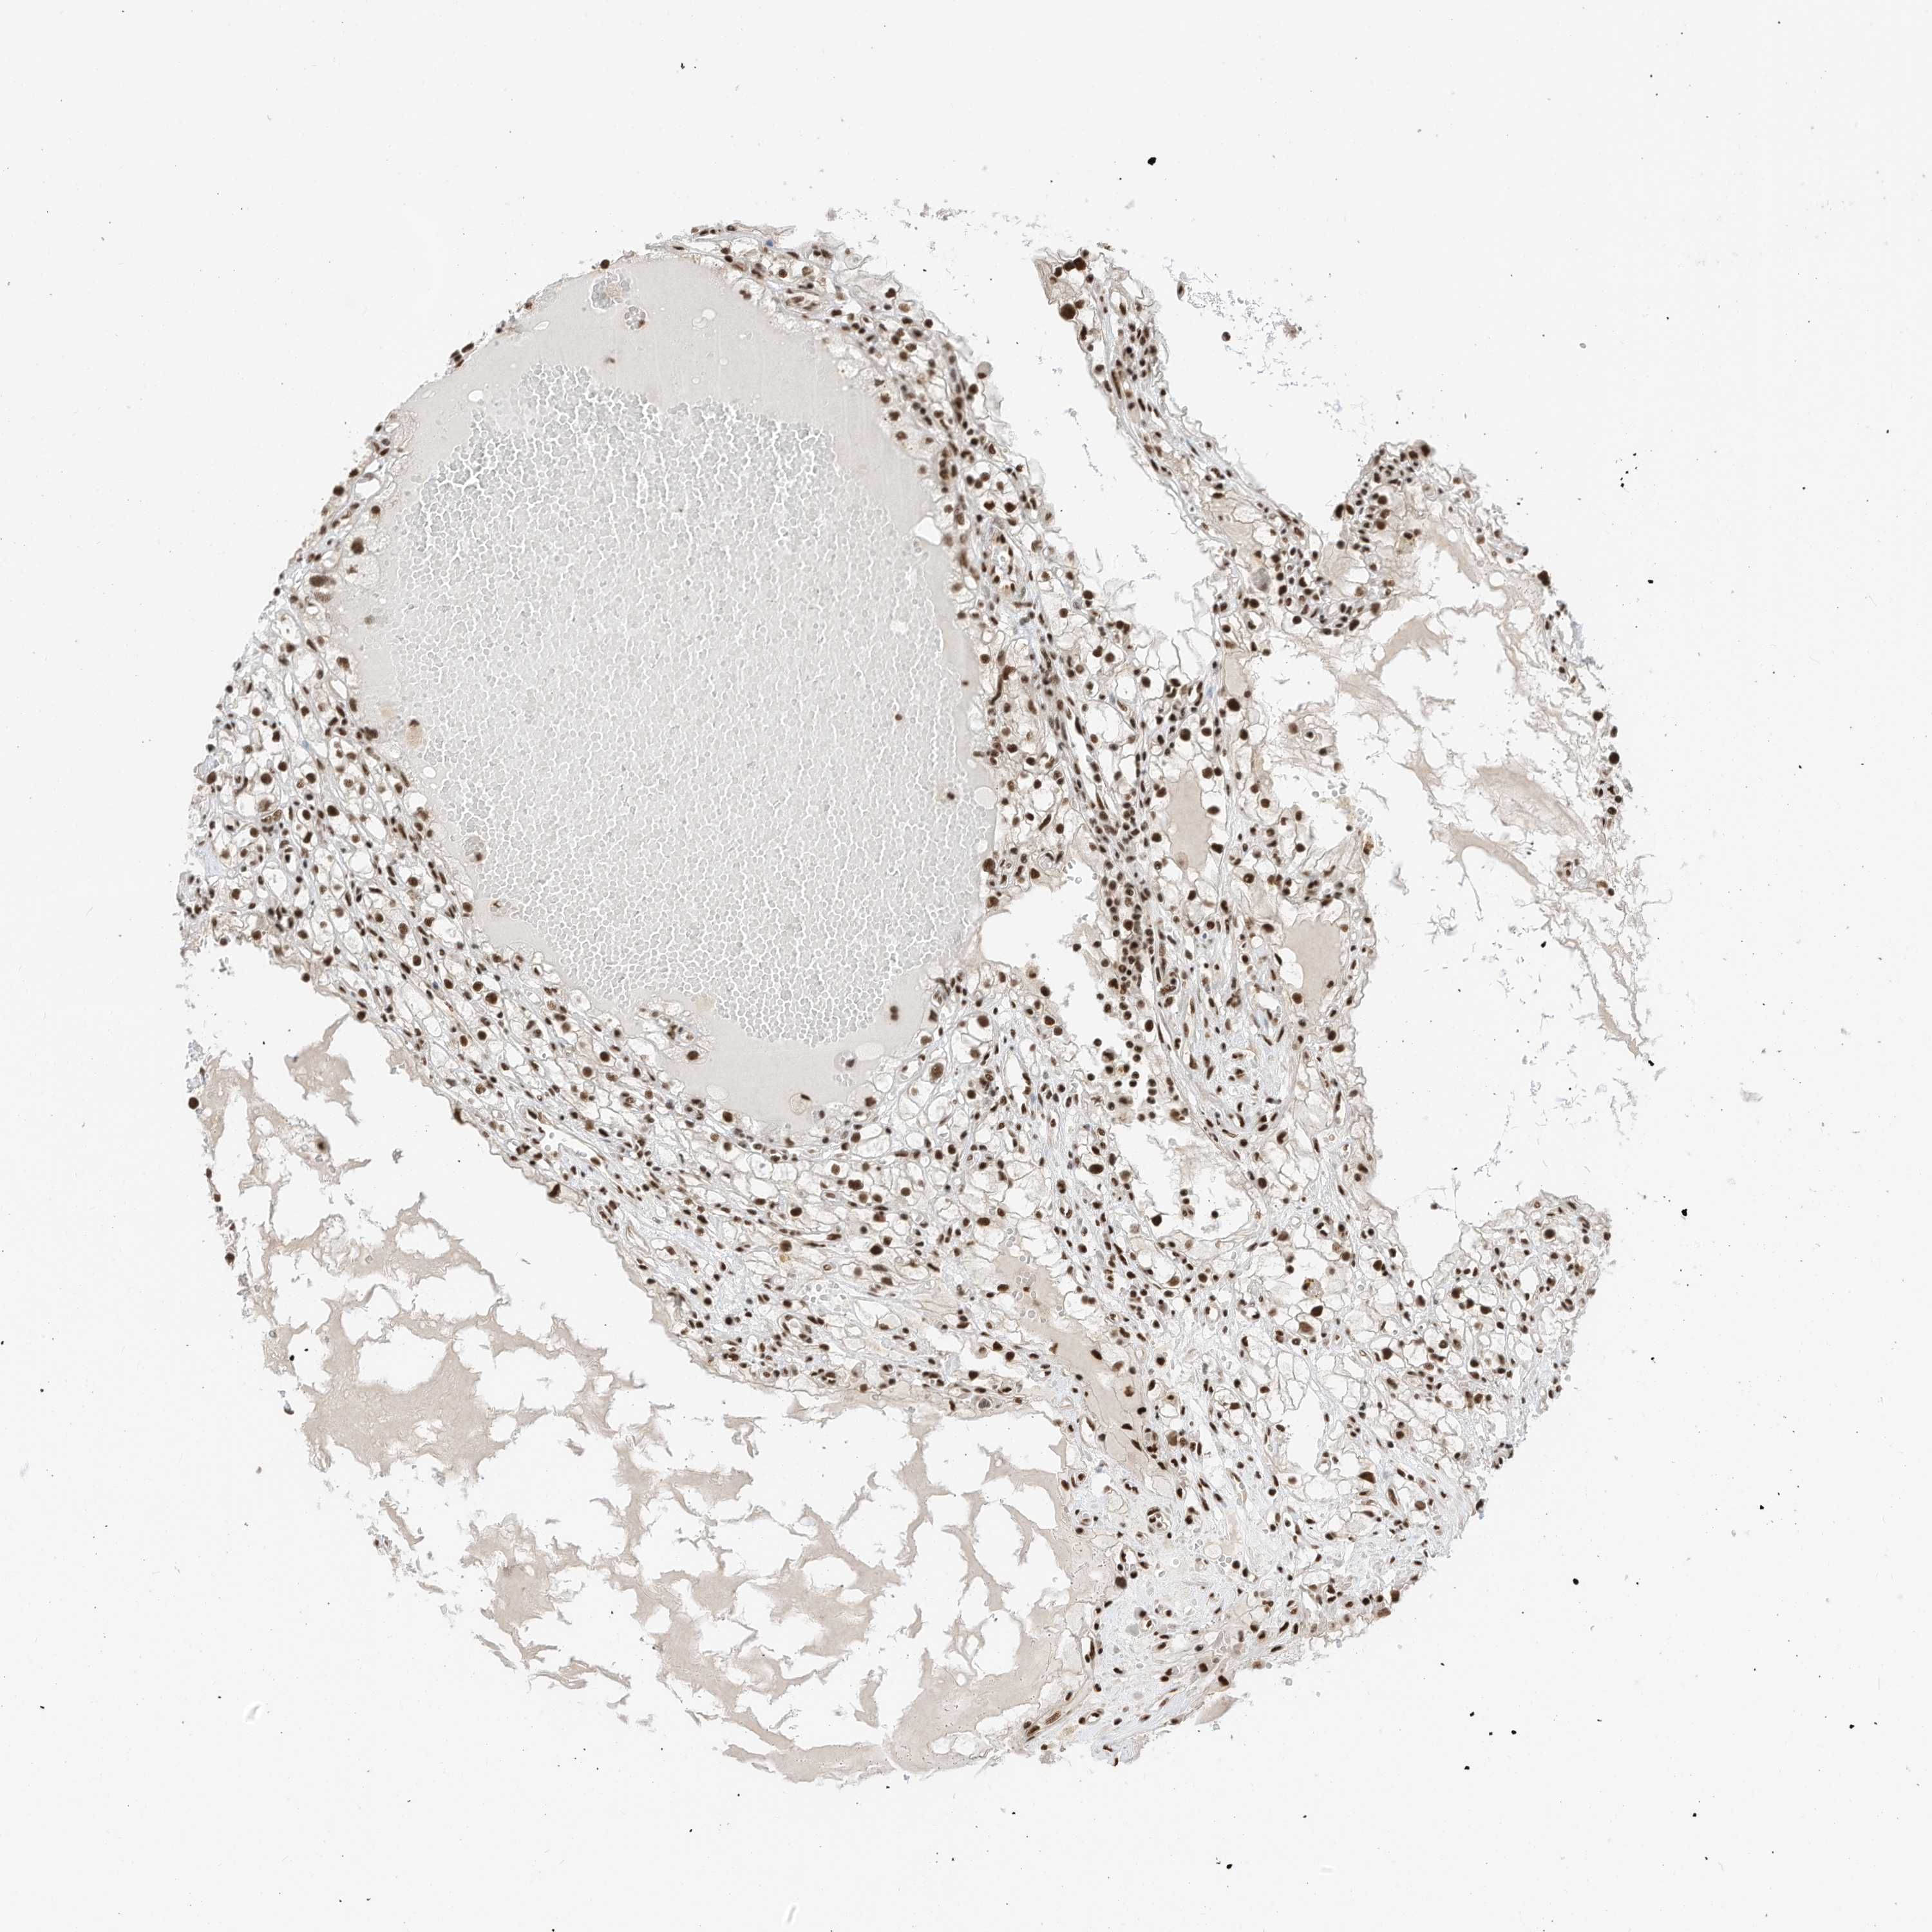

KIDNEY RENAL CLEAR CELL CARCINOMA (VALIDATION) - Interactive survival scatter ploti

SF3A3 is not prognostic in Kidney Renal Clear Cell Carcinoma (validation)

: 37.08

Average pTPM 35.4

Number of samples 100